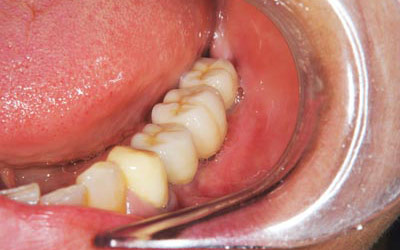

さらに、インプラントが骨としっかりと結合するのを待って、被せものを完成させました。